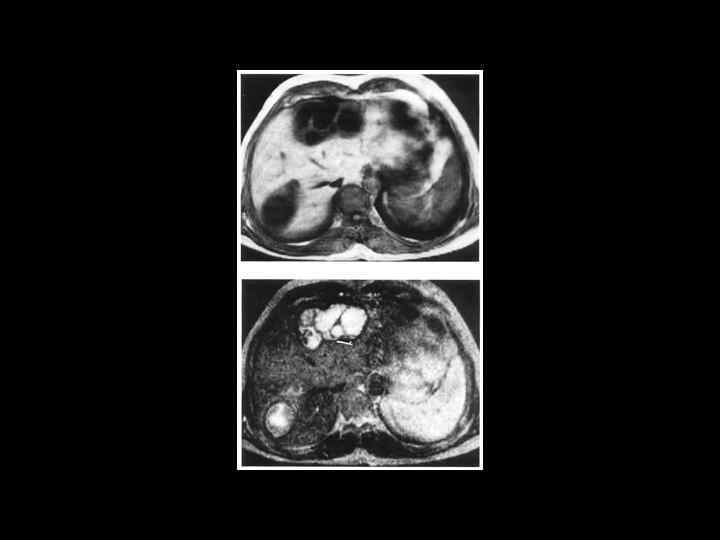

АКТУАЛЬНЫЕ ВОПРОСЫ РЕНТГЕНОЛОГИИ ЛУЧЕВАЯ ДИАГНОСТИКА ОЧАГОВЫХ ПОРАЖЕНИЙ ПЕЧЕНИ Кавернозная гемангиома печени МР- семиотика: - образование с гиперинтенсивным сигналом на Т-2 взвешенном изображении -после введения контрастного вещества- динамика изменений такая же, как при КТ

АКТУАЛЬНЫЕ ВОПРОСЫ РЕНТГЕНОЛОГИИ ЛУЧЕВАЯ ДИАГНОСТИКА ОЧАГОВЫХ ПОРАЖЕНИЙ ПЕЧЕНИ ЭХИНОКОККОВЫЕ КИСТЫ УЗИ: краевые кольцевидные обызвествления КТ: низкоплотностные образования с перегородками и четкими контурами МРТ: образования дающие гиперинтенсивный сигнал на Т 2 взвешенных изображениях